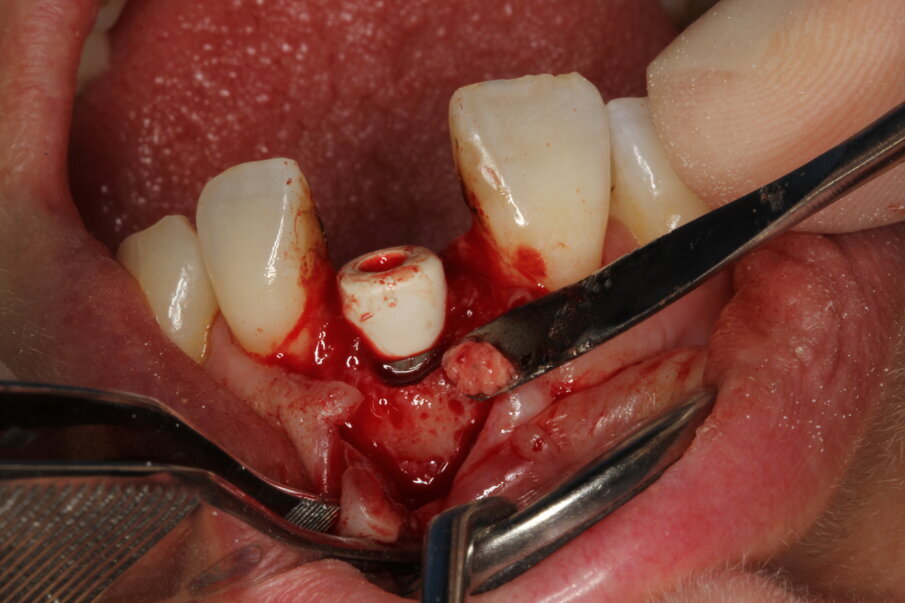

Surgery

Local anaesthesia was performed with 2% mepivacaine with 1:100,000 adrenaline. Preventative antibiotic therapy with amoxicillin (1 g, b.d. for five days) was prescribed, aided by use of a 0.2 % chlorhexidine mouthrinse three times a day for one minute. The tooth was extracted and the sulcular epithelium removed with diamond burs. The milled surgical template (Figs. 12 & 13) served as a guide for the first 2 mm diameter pilot drill (Fig. 14). Thus, the planned depth, position and angulation of the osteotomy were obtained. The drill sequence was completed freehand, using tapered 3.0 and 3.4 mm drills. A Neoss Pro- Active Tapered Implant of 4 mm in diameter and 13 mm in length was inserted flush with the mesial/palatal/distal bone, motor driven up to a torque of 50 Ncm and then with a manual wrench (Fig. 15). The correct position of the internal hex was verified by checking the references on the implant driver, which ideally points in the buccal direction. Resonance frequency analysis with Penguin RFA (Integration Diagnostics Sweden) determined an ISQ value of 73/76. At this stage, a Neoss Esthetic Healing Abutment with a ScanPeg was connected to the implant (Fig. 16). A flap was then raised after a vertical incision of the frenulum and the expected buccal exposure of the implant neck was evident. Autogenous bone harvested from the drills was positioned directly on the implant surface (Fig. 17), followed by a bone substitute on top of it and on the buccal cortical bone (Fig. 18). This material was covered with a resorbable membrane (Fig. 19). The mobilised flap was then repositioned by rotating it coronally and fixed with single sutures (Fig. 20). The removable partial denture was adapted and delivered (Fig. 21). An immediate postoperative CBCT scan of 60 x 60 mm was performed, and it confirmed a perfectly centred implant position (Figs. 22 & 23).